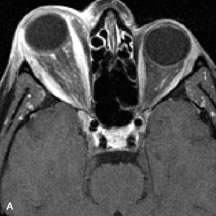

Metastatic Tumors

Breast carcinoma metastatic to the orbit has been demonstrated to be hypointense to the surrounding orbital fat on T1-weighted studies and hyperintense on T2-weighted images and has an affinity to the extraocular muscles (Fig. 20).50,64 The MRI characteristics of prostate carcinoma metastatic to the orbit have been described as involving the greater and lesser wing of the sphenoid, orbital roof, and optic canal. Diffuse bone hypertrophy with isointense or slightly hyperintense tissue on T1-weighted images represents the osteoblastic carcinomatous bone infiltration. Contrast enhancement is variable on T1-weighted and fat-suppressed images.65

Fig. 20. A. T1-weighted MR scan demonstrates nodular enlargement of both medial rectus muscles (arrows). B. T1-weighted fat-suppressed contrast-enhanced scan confirms the presence of small metnstatic deposits within the muscles (open arrows).